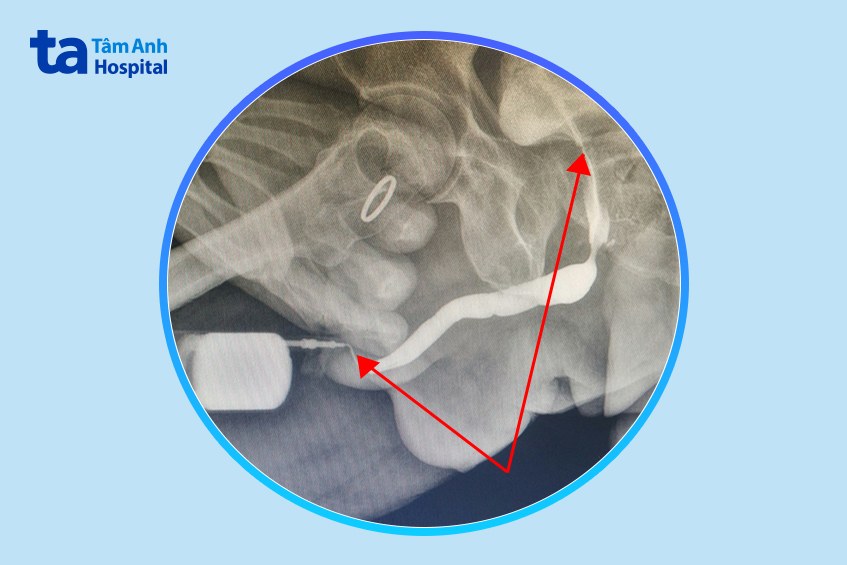

Để chụp X-quang niệu đạo ngược dòng đánh giá mức độ hẹp niệu đạo, bác sĩ Liên phải sử dụng ống 8 Fr (khoảng 2,5 mm) mới đưa qua được lỗ niệu đạo của người bệnh, trong khi đường kính lòng trong niệu đạo bình thường của nam giới là 20-30 Fr.

Bác sĩ cho biết thêm ngoài miệng niệu đạo, ông Q. còn có một đoạn hẹp niệu đạo khác do tuyến tiền liệt phì đại chèn ép vào.